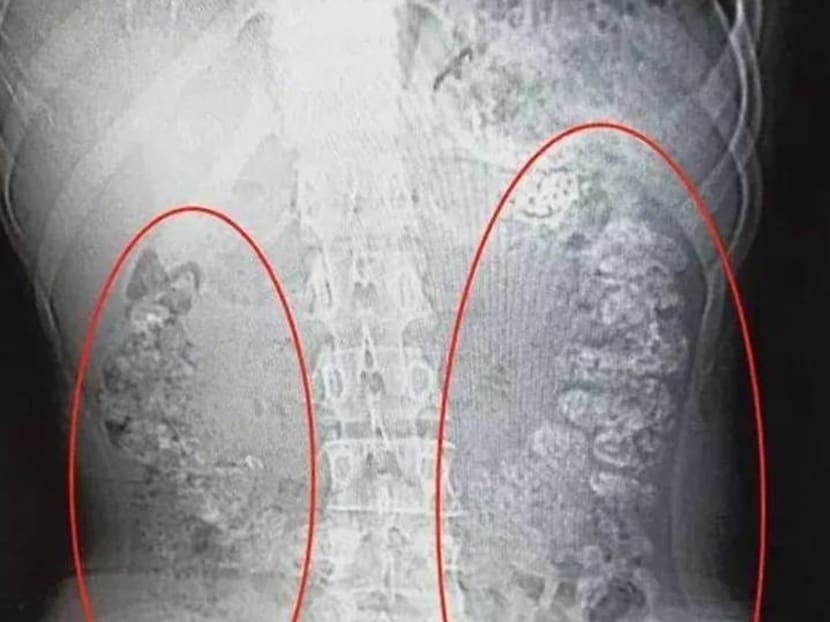

A 14-year-old girl in Zhejiang, China recently went viral for her hospital X-ray scan, which apparently revealed hundreds of undigested bubble tea pearls clustered in her body.

So 8days.sg investigated and showed our general practitioner the X-ray scan. We learnt that the sinister-looking granules are actually not tapioca pearls as widely believed, but lumps of impacted faeces. Oh, crap.

The GP, who declines to be named, paints a graphic picture: “The X-ray shows that the patient’s body is full of faeces. Pearls are made of tapioca starch, which is glue-like. The pearls that are not digested well combine with other foods consumed and cause faeces to become sticky, which leads to partial or total bowel obstruction.”

After a CT scan of the girl’s abdominal region, the hospital’s Dr Zhang Louzhen examined the X-ray results and was surprised to find granular shadows filling most of her organs, from the stomach to the colon and anus.